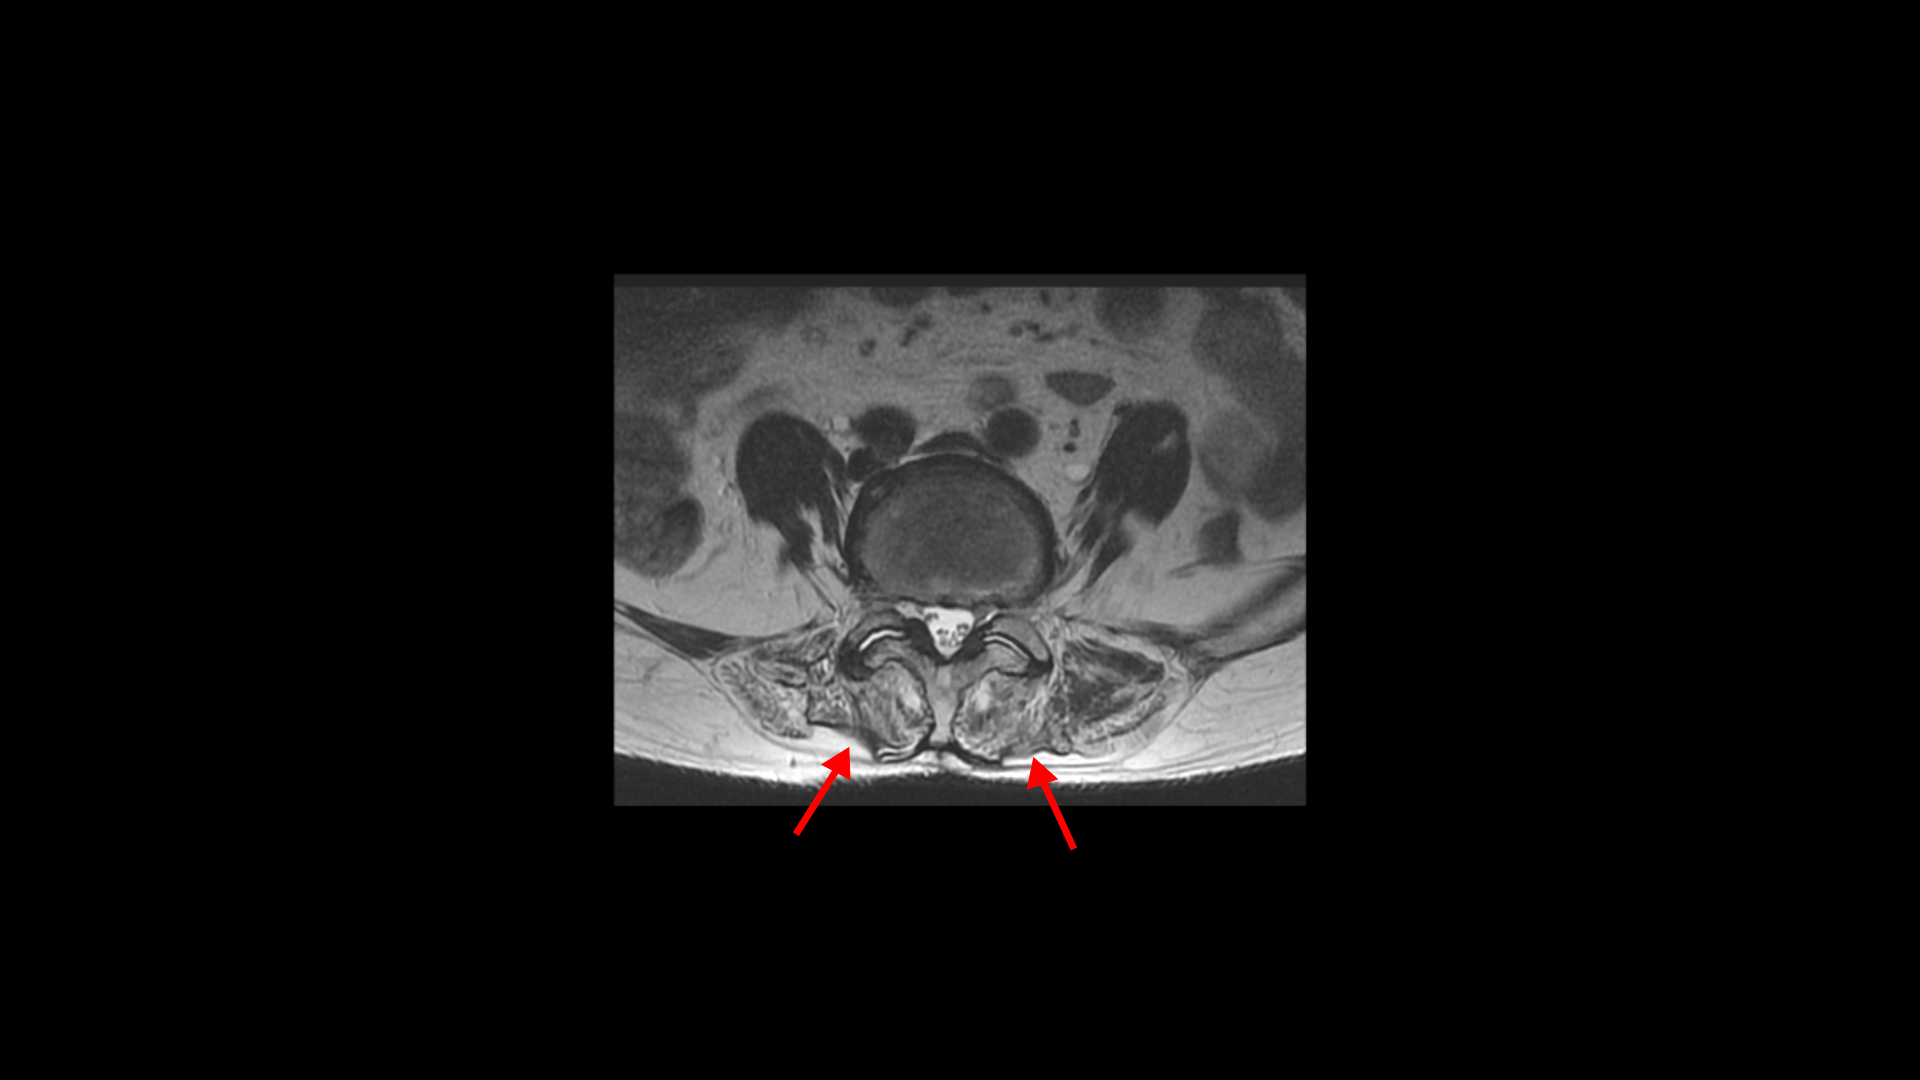

이 환자분의 일어서면 허리가 구부러지고 다리가 아파 걷기 어려운 이유는 근감소증 때문입니다. 특히 근육 중에서도 MRI에서 보면 허리 뒷부분에서 허리를 펴주는 근육인 기립근이 보시다시피 하얗게 지방으로 변해있습니다.

이분하고 증상이 비슷한 다른 근감소증 환자분의 기립근도 마찬가지입니다.

이분도 근감소증 치료후기가 있으니까 꼭 보세요. 이렇게 기립근이 지방으로 심하게 변해버린 분들은 허리를 펴주고 세워주는 근육의 기능이 떨어지니까 일어서서 걸으려고 하면 허리가 그냥 앞으로 구부러져 버리는 것입니다.